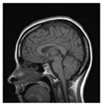

The encrypted marked image is decrypted to reconstruct the marked image as shown in Figure 3. Then, the marked one is verified. This is shown in the following stages:

Figure 3.

Verification process.

Stage 1: The encrypted marked image is decrypted using DRPE to obtain a marked image.

Stage 2: 2D-DWT is applied to the marked image to generate four sub-bands LL, HL, LH, and HH. Four sub-bands are divided into (8 × 8) blocks; then, DCT is applied to each block.

Stage 3: Working from right to left, bottom to top, embedded rows and columns are extracted and compared to their corresponding cones through a correlation analysis.

Stage 4: Embedded rows and columns are extracted and compared to their corresponding cones through a correlation analysis.